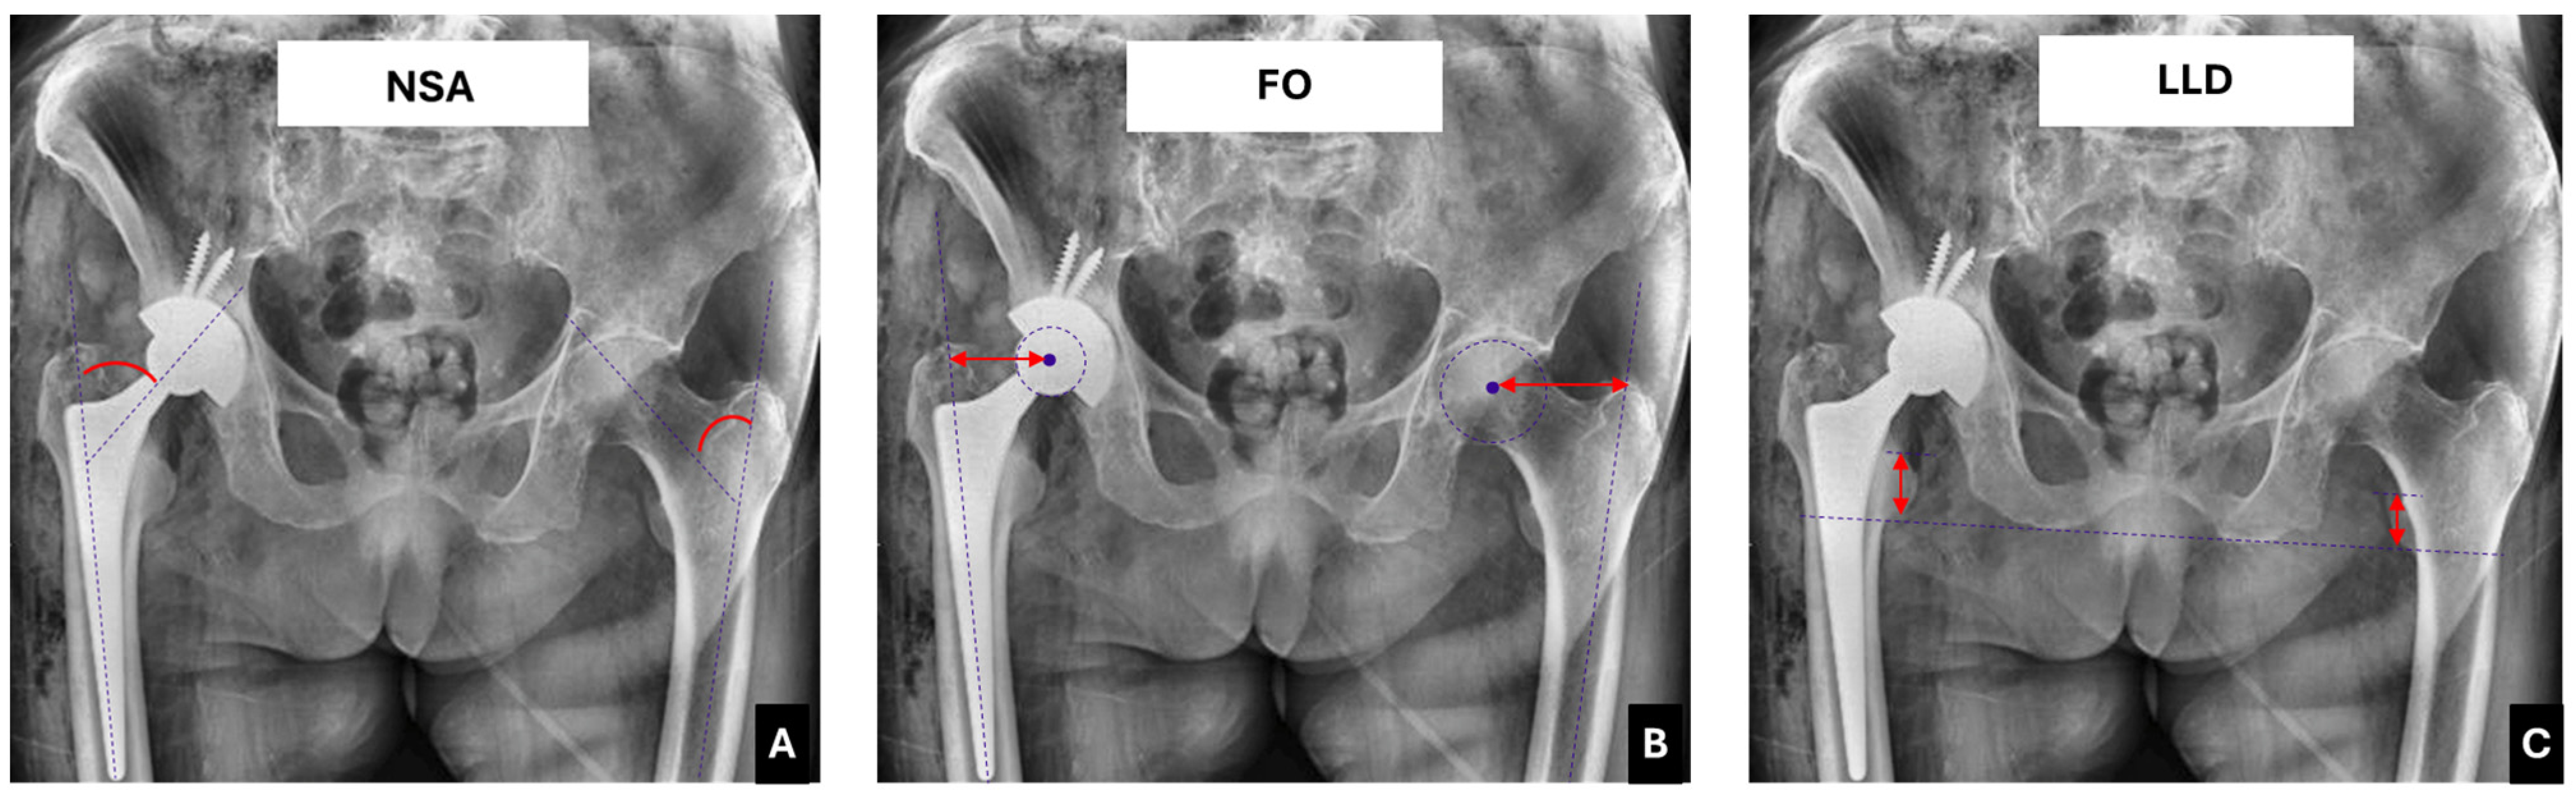

| Neck shaft angle (NSA) | 127.7 ± 5.6° | 135.1 ± 2.4° | 7.4 ± 2.6° | <0.001 * |

| Femoral offset (FO) | 42.4 ± 2.7 mm | 51.4 ± 7.42 mm | 9 ± 3.2 mm | <0.001 * |

| Limb length discrepancy (LLD) | - | - | 8.35 ± 2.25 mm | - |